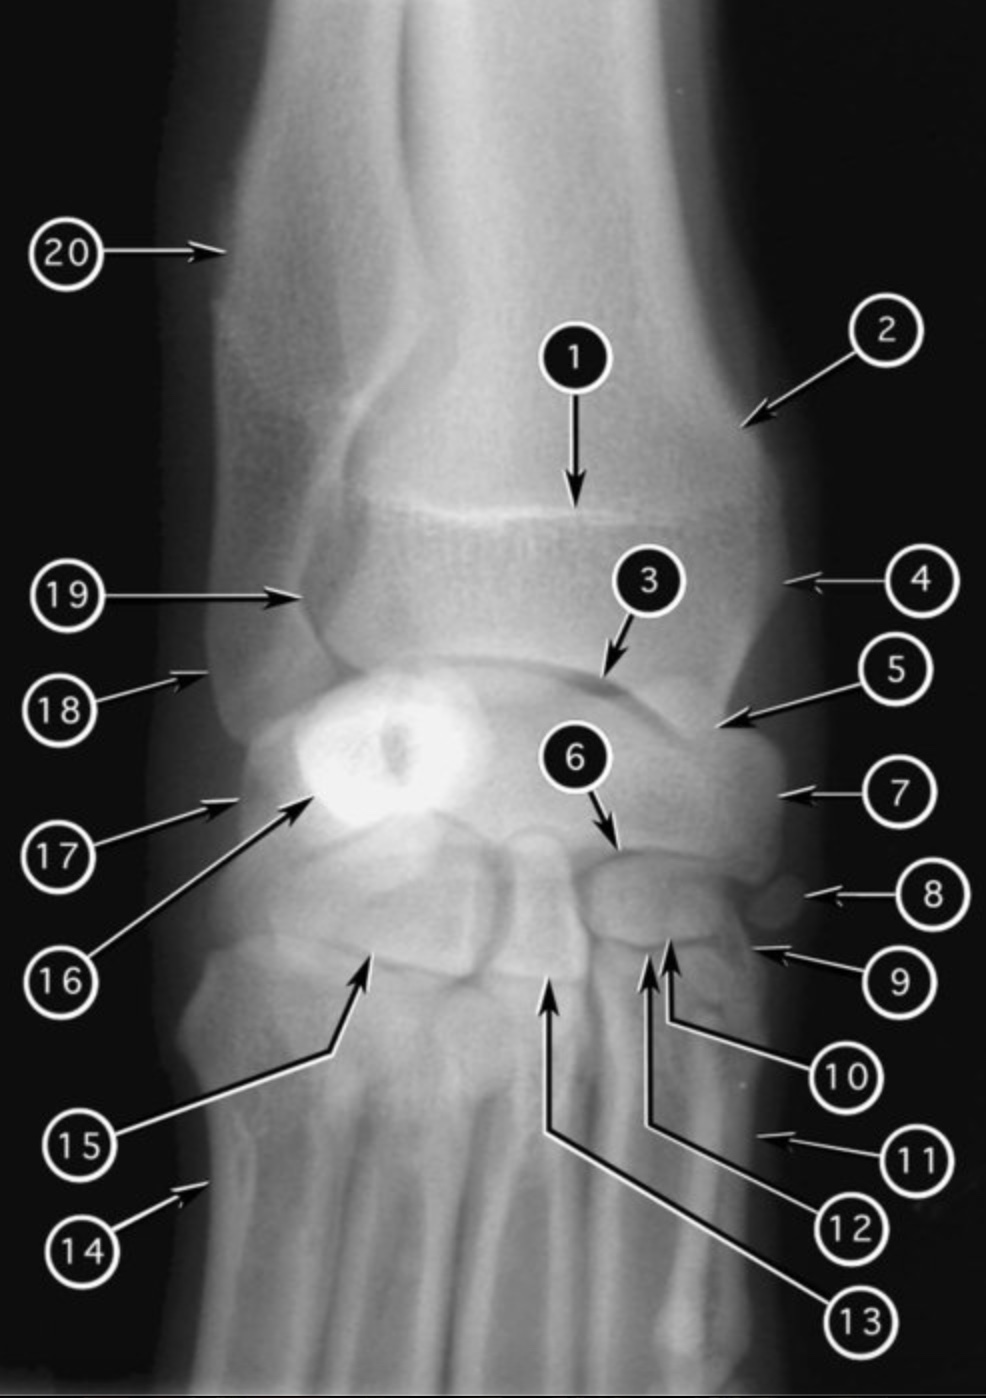

joint #3?

antebrachiocarpal joint

New cards

joint #19?

distal radioulnar joint

joint #6?

midcarpal joint

joint #12?

carpo-metacarpol joint